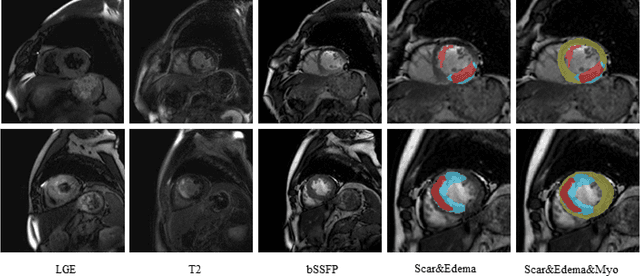

Abstract:Multi-sequence cardiac magnetic resonance (CMR) provides essential pathology information (scar and edema) to diagnose myocardial infarction. However, automatic pathology segmentation can be challenging due to the difficulty of effectively exploring the underlying information from the multi-sequence CMR data. This paper aims to tackle the scar and edema segmentation from multi-sequence CMR with a novel auto-weighted supervision framework, where the interactions among different supervised layers are explored under a task-specific objective using reinforcement learning. Furthermore, we design a coarse-to-fine framework to boost the small myocardial pathology region segmentation with shape prior knowledge. The coarse segmentation model identifies the left ventricle myocardial structure as a shape prior, while the fine segmentation model integrates a pixel-wise attention strategy with an auto-weighted supervision model to learn and extract salient pathological structures from the multi-sequence CMR data. Extensive experimental results on a publicly available dataset from Myocardial pathology segmentation combining multi-sequence CMR (MyoPS 2020) demonstrate our method can achieve promising performance compared with other state-of-the-art methods. Our method is promising in advancing the myocardial pathology assessment on multi-sequence CMR data. To motivate the community, we have made our code publicly available via https://github.com/soleilssss/AWSnet/tree/master.